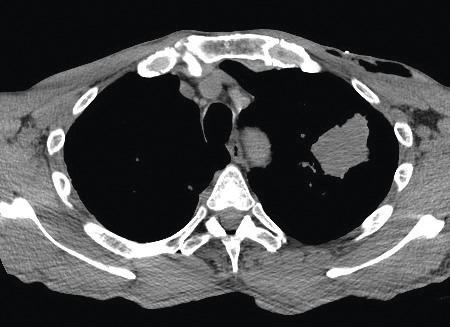

Un scanner thoracique met en évidence une masse apicale gauche de 3 cm et une seconde, lobaire inférieure gauche (fig. 2).